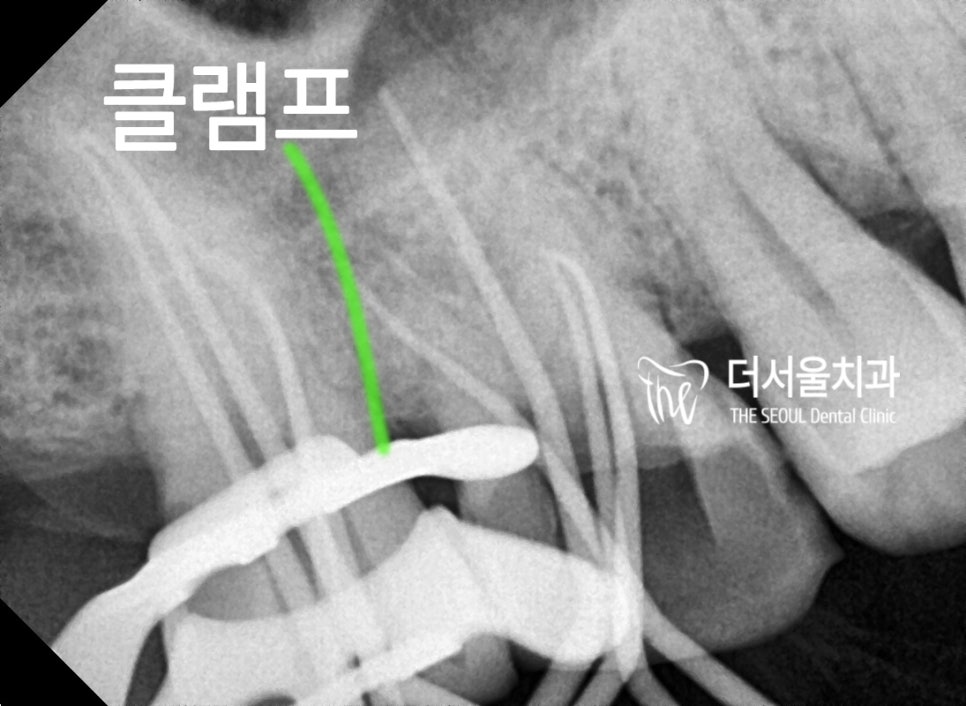

신경치료에서 있어서 핵심은

‘방습환경’ 을 갖추는 겁니다.

이 때 필요한 것이

첫번째, 러버댐

두번째, 클램프

입니다.

마찬가지로, 방습환경을 갖추려

클램프 및 러버댐을 이용해서

치수 밀폐를 진행하는 사진입니다.

치아 뿌리 끝(apex)까지 꼼꼼히

밀폐되고 있는 과정을 보고 계십니다.

이 다음에는 이제 레진코어 를